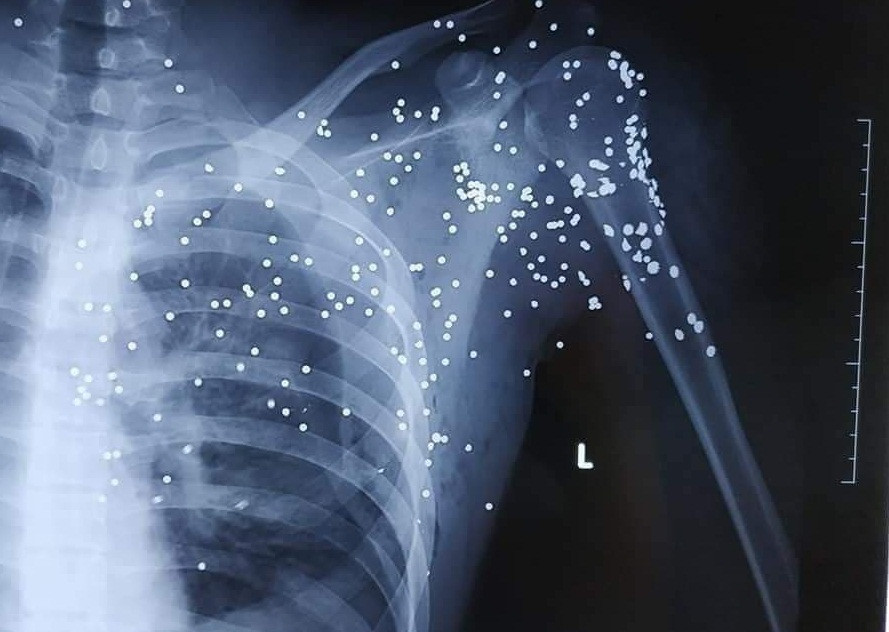

Những vết thương chi chít của nạn nhân khi bị bắn bằng súng hoa cải.

Trước đó, vào khoảng 20h30 ngày 23/11, anh Bùi Huy Hoàng (19 tuổi, trú tại xã Bình Minh, Kiến Xương, con trai của chủ nhà xe Trường Kỳ chạy tuyến Thái Bình - Hà Nội) bị một người lạ mặt đi xe khách cầm súng hoa cải bắn trúng người tại khu vực trạm BOT Thanh Nê.

Gây án xong, hung thủ bỏ trốn khỏi hiện trường. Anh Hoàng bị đa chấn thương nhập viện trong tình trạng nguy kịch với nhiều vết đạn ở vùng cổ, vai và ngực trái. Nạn nhân sau đó được chuyển từ Bệnh viện Đa khoa tỉnh Thái Bình lên cấp cứu tại Bệnh viện Việt Đức (Hà Nội).

Trước đó, vào khoảng 20h30 ngày 23/11, anh Bùi Huy Hoàng (19 tuổi, trú tại xã Bình Minh, Kiến Xương, con trai của chủ nhà xe Trường Kỳ chạy tuyến Thái Bình - Hà Nội) bị một người lạ mặt đi xe khách cầm súng hoa cải bắn trúng người tại khu vực trạm BOT Thanh Nê. Gây án xong, hung thủ bỏ trốn khỏi hiện trường. Anh Hoàng bị đa chấn thương nhập viện trong tình trạng nguy kịch với nhiều vết đạn ở vùng cổ, vai và ngực trái.